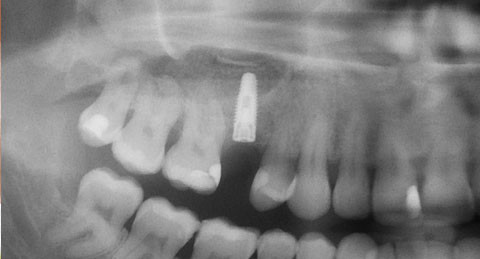

Der Lappen wurde nach Periostschlitzung readaptiert und der Zugang mittels Naht speicheldicht verschlossen (16 x Supolene 4.0; Fa. Resorba). Das Kontrollröntgenbild zeigt die achsengerechte Position des Implantates bei gleichzeitig guter Kontrollübersicht des augmentierten Sinus maxillaris (Abb. 10). Die Patientin wurde antibiotisch abgeschirmt und zur postoperativen Nachsorge bis hin zur Nahtentfernung bei komplikationslosem Verlauf einbestellt.